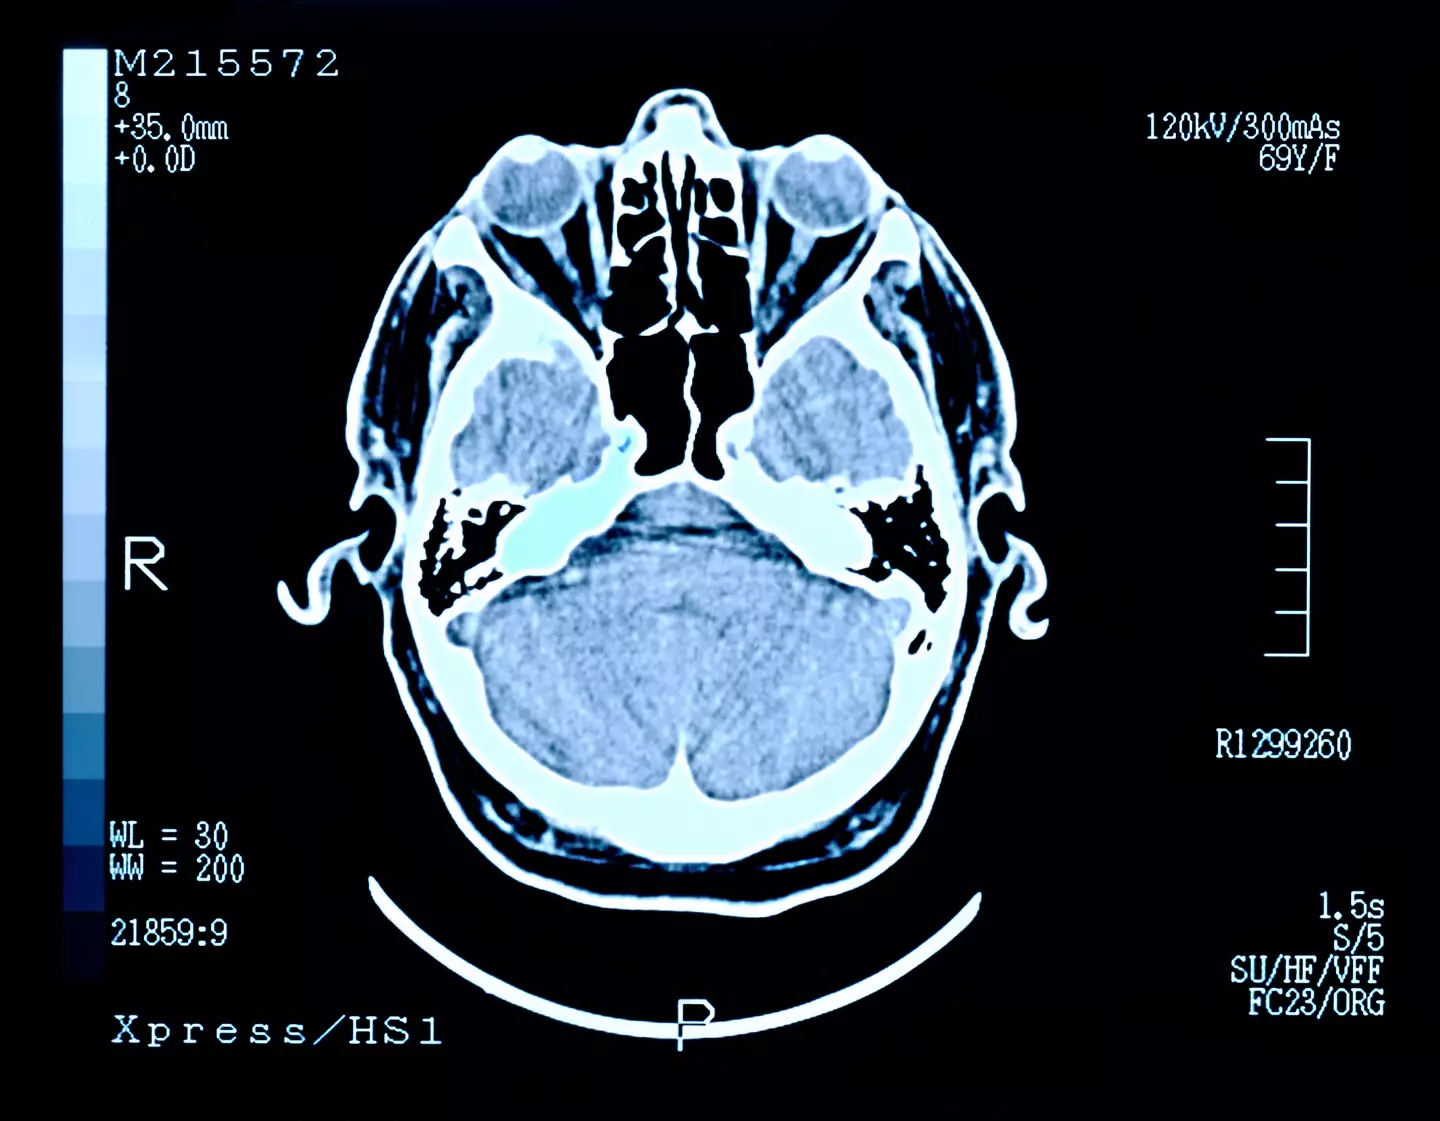

In the study, scientists mapped out the brain activity of four people while they were dying, and found bursts of activity in their brains after their hearts stopped.